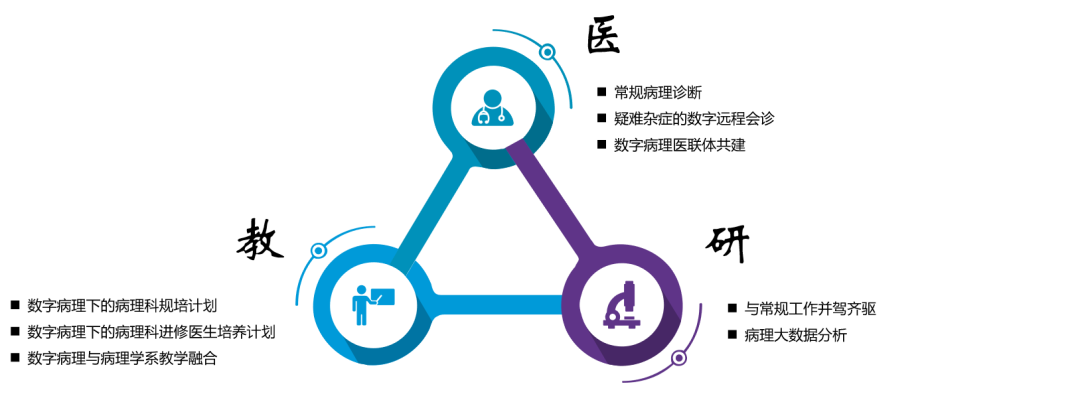

数字化病理科建设模块介绍

数字化建设模块图

来源:蛋壳研究院